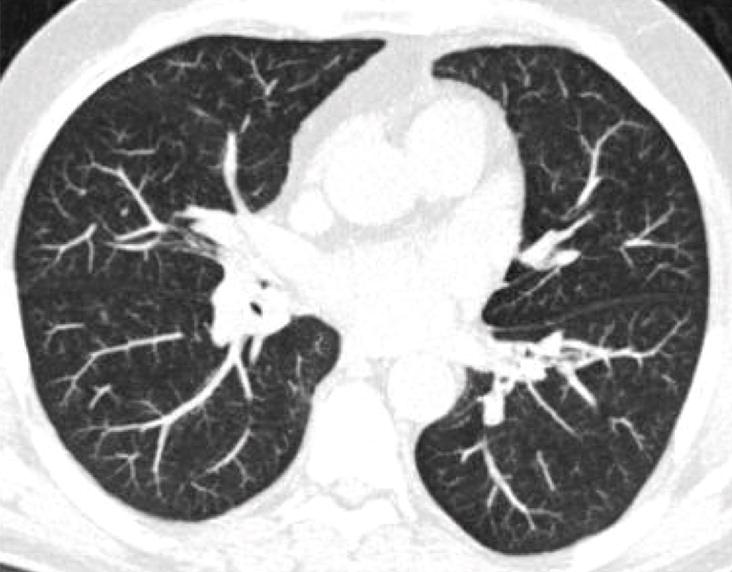

About 10% of solid intraparenchymal nodules of intermediate size resolve during followup

Short term followup CT valuable for detecting fast-growing nodules and for identifying 3/4 of resolving nodules